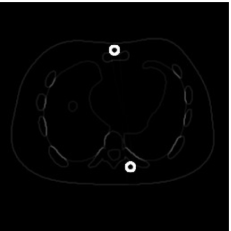

4.2 Numerical experiments: real data

We perform a CT scan of a chicken leg placed in a disposable cup (Figure 10(a)). We first scan the chicken leg without metals (Figure 10(b)) to create a reference image using FBP algorithm. Then, we place two steel thread nails on each side of the chicken leg and scan the subject again using the same scanning protocol (Figure 10(c)). The projection data is acquired from a MicroCT scanner equipped at the Division of Nuclear Technology and Applications, Institute of High Energy Physics, Chinese Academy of Sciences. The X-ray source is with 90 kV and 70 mA energy and the flat plane detector contains pixels. The scanning trajectory is a full circle with equally spaced views at per view. The physical size of each detector unit is . The distance from the X-ray source to the detector is . In order to conduct a 2D experiment, we choose the 512th row of the detector array.

Figure 11 shows the images reconstructed using FBP, the analysis model (2.12), the inpainting model (2.13) and the segmented image from the image obtained by (2.14). The reference image without metal implants are shown in Figure 11(a). All the images in this subsection are displayed within the grayscale interval . The segmented image shown in Figure 11(e) is used to estimate the weights needed in NMAR and the re-weighted JSR model.